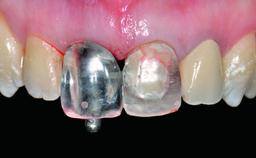

Replacement of a Missing Upper Left Central Incisor, Late Placement of an RC Bone Level Implant and Adjacent Tooth Restoration

A healthy 38-year-old male patient was referred for replacement of a failing tooth-supported cantilever fixed dental prosthesis on teeth 11 and 21. The patient reported a history of trauma at 13 years of age that had resulted in the subsequent loss of tooth 11, as well as endodontic treatment of the adjacent abutment tooth 21. A metal-ceramic cantilever fixed dental prosthesis replacing tooth 11 had been provided by his general dentist several years after the loss of the tooth, with tooth 21 as the sole abutment. At the time of initial presentation, this restoration had been in service for over 20 years.